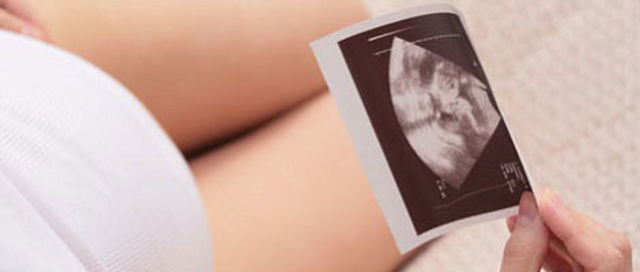

la cara tiene perfil humano, la barbilla ha crecido. Las orejas aún ocupan una posición baja y las uñas empiezan a crecer.

Los genitales tienen características femeninas y masculinas en función del sexo del nuevo ser aunque aún no se han formado por completo, por lo que todavía no es fácil aclarar el sexo.

La cara va adquiriendo una forma más normal y redondeada, los ojos que están muy separados se juntan un poco, y también suben un poco las orejas llegando casi hasta su situación definitiva, ya que cuando se forman están muy baja, ya existe un primordio del intestino, se llaman asas intestinales, Al final de esta semana las medidas del feto son: 8,5 cm de longitud y su peso oscila entre 15 y 20 gramos.